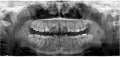

Была на приеме у одного стоматолога, сказал, что нужно удалять нижние восьмерки, одна из них - разрушена. Не больно постучали по нижней левой восьмерке, я выплюнула кусочки зуба. Пошла к другому стоматологу-хирургу, сделала панорамный снимок, сказал, что нужно удалять верхние восьмерки (сказал, что корни целые, но сами зубы - разрушены).

Скажите, пожалуйста, насколько это возможно, какие зубы нужно удалять?